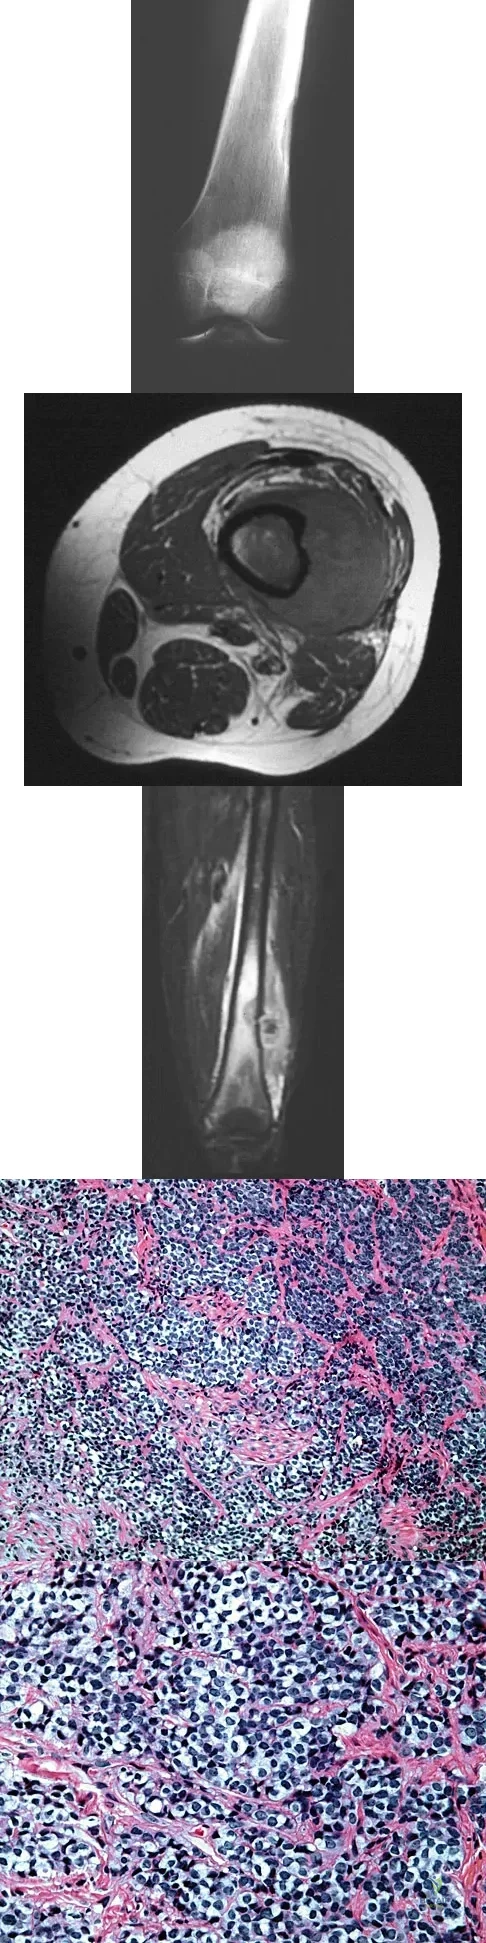

A 16-year-old boy has had left knee pain and swelling after sustaining a minor twisting injury while playing basketball 2 weeks ago. Figures 5a through 5e show the radiograph, MRI scans, and biopsy specimens. What is the most likely diagnosis?

Explanation